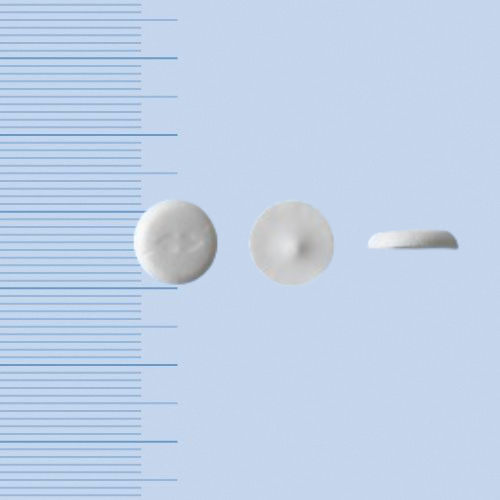

ミニリンメルトOD錠120μg

デスモプレシン酢酸塩水和物口腔内崩壊錠

仕様

【成分】

[1錠中]

デスモプレシン酢酸塩水和物 133μg

(デスモプレシンとして120μg)

デスモプレシン酢酸塩水和物口腔内崩壊錠